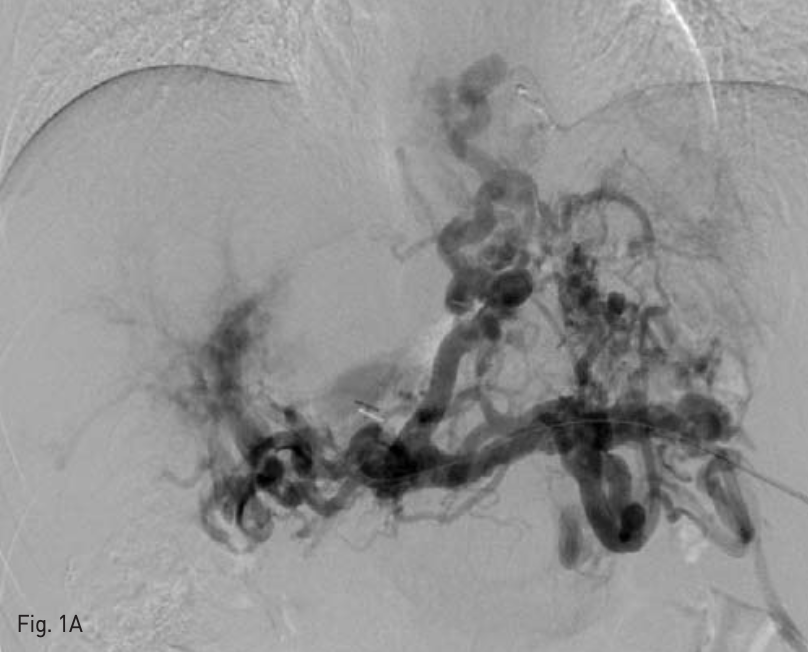

초음파와 투시 유도 하에 국소 마취 후 비장 정맥을 21G Chiba needle(TSK laboratory, Soja, japan)로 puncture한 후 6-Fr sheath(Radiofocus, Terumo,

Tokyo. Japan)를 삽입하였다. 5-Fr Davis catheter(Cook medical, Bloomington, IN, USA)를 이용하여 정맥조영술을 시행하였으며, multiple feeder로부터 flow를 받는 esophageal varix가 조영 되었다(Fig. 1A).

A. Percutaneous transsplenic portography shows diffuse development of tortous esophageal varix with multiple collateral channels.